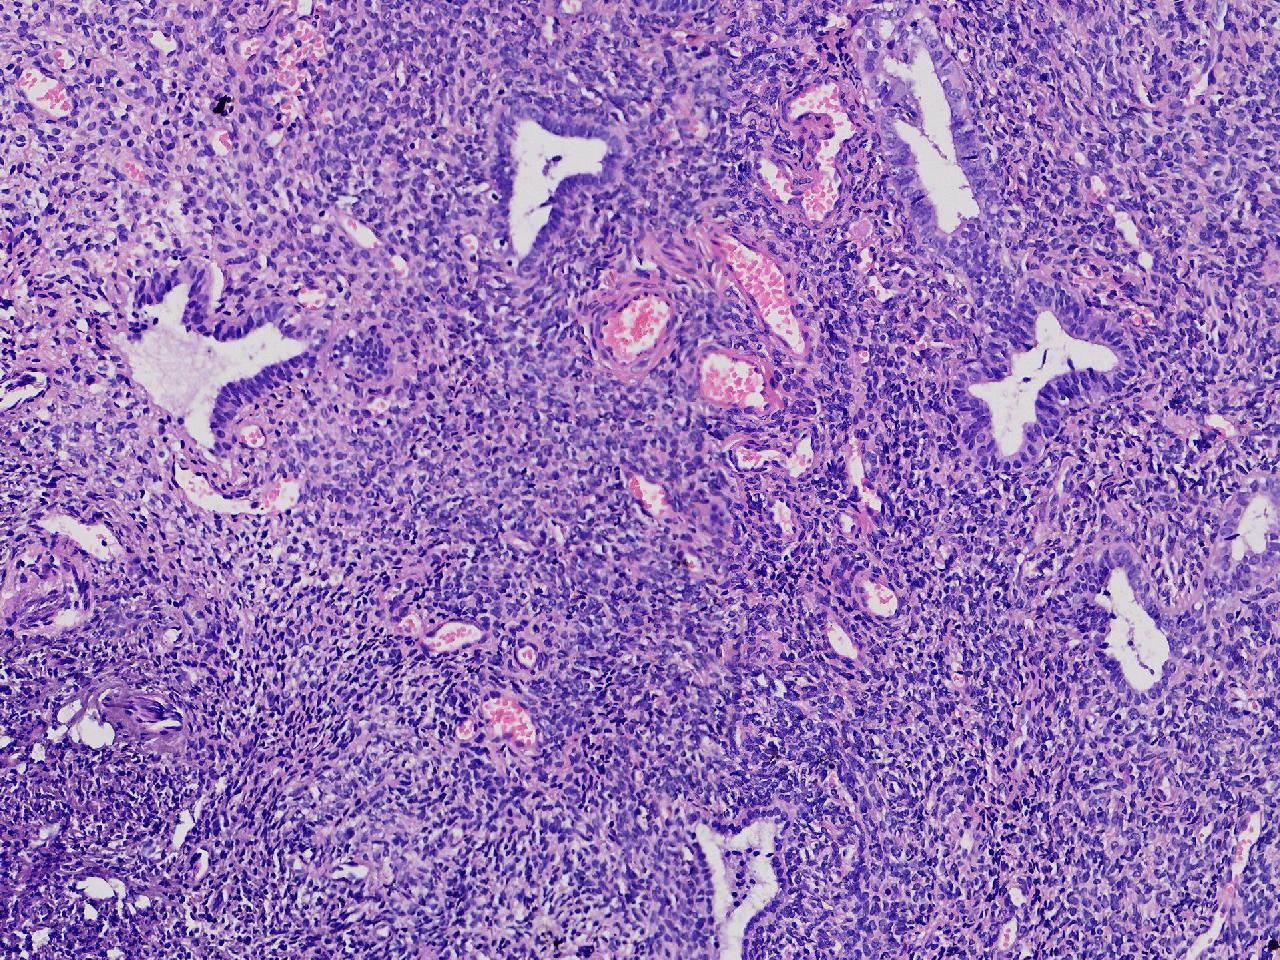

性别

女

年龄

56岁

彩超示宫腔内见5x3ml的团状偏强回声结节,边界清。

宫腔息肉?

灰粉色不整形软组织多块,0.5X0.3X0.3厘米。

首先考虑子宫内膜息肉,有些区域间质细胞较密,找找看有没有核分裂。

彩超提示强声团体积不小,待完整切除送检再综合诊断。